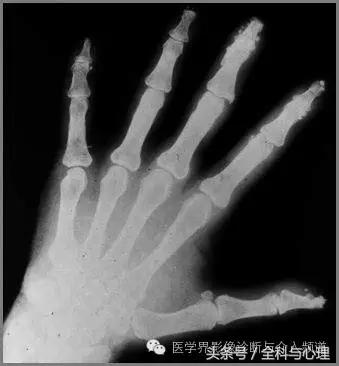

2、 与硬皮病相关的手部局限性钙质沉积

手部皮肤或皮下组织,多发的,边界清晰的,点状、片状的钙化灶,与硬皮病相关。

硬皮病